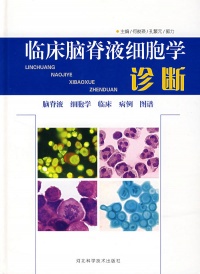

脑脊液

成人正常白细胞数在0.01×109个/L以下(早产儿及新生儿在0.03×109个/L以内),但多核白血球9不应超过5个,主要为小、中淋巴细胞。当脑膜有刺激性或炎性病变时,脑脊液的白血球计数即可增多。故中枢神经系统感染性病变时,有多核或单核细胞的不同程度的增高;各种脑部肿瘤特别是临近脑膜、脑室或恶性者,也有白血球的增多。

使用特殊的脑脊液细胞离心沉淀器,将浓集于玻片上的细胞给以各种染色,还可细致观察到细胞的形态改变,大大提高了诊断效果,如嗜伊红细胞增高提示有中枢神经系统寄生虫病;内有含铁血黄素的吞噬细胞提示脑脊液中有陈旧出血等。此外,还可直接观察到肿瘤细胞和寄生虫卵等,以及对细胞进行免疫功能的研究。

细胞计数及分类: 脑脊液中正常无红细胞,仅有少数白细胞(淋巴细胞).

化脑:细胞数可达1000×106/L, 以中性粒细胞为主。

结脑:细胞数<500×106/L, 早期以中性粒细胞为主, 后期以淋巴细胞为主, 中性粒细胞, 淋巴细胞和浆细胞同时存在为特征。

病脑:细胞数 几十×106/L, 以淋巴细胞为主。

脑膜白血病:幼稚细胞 。